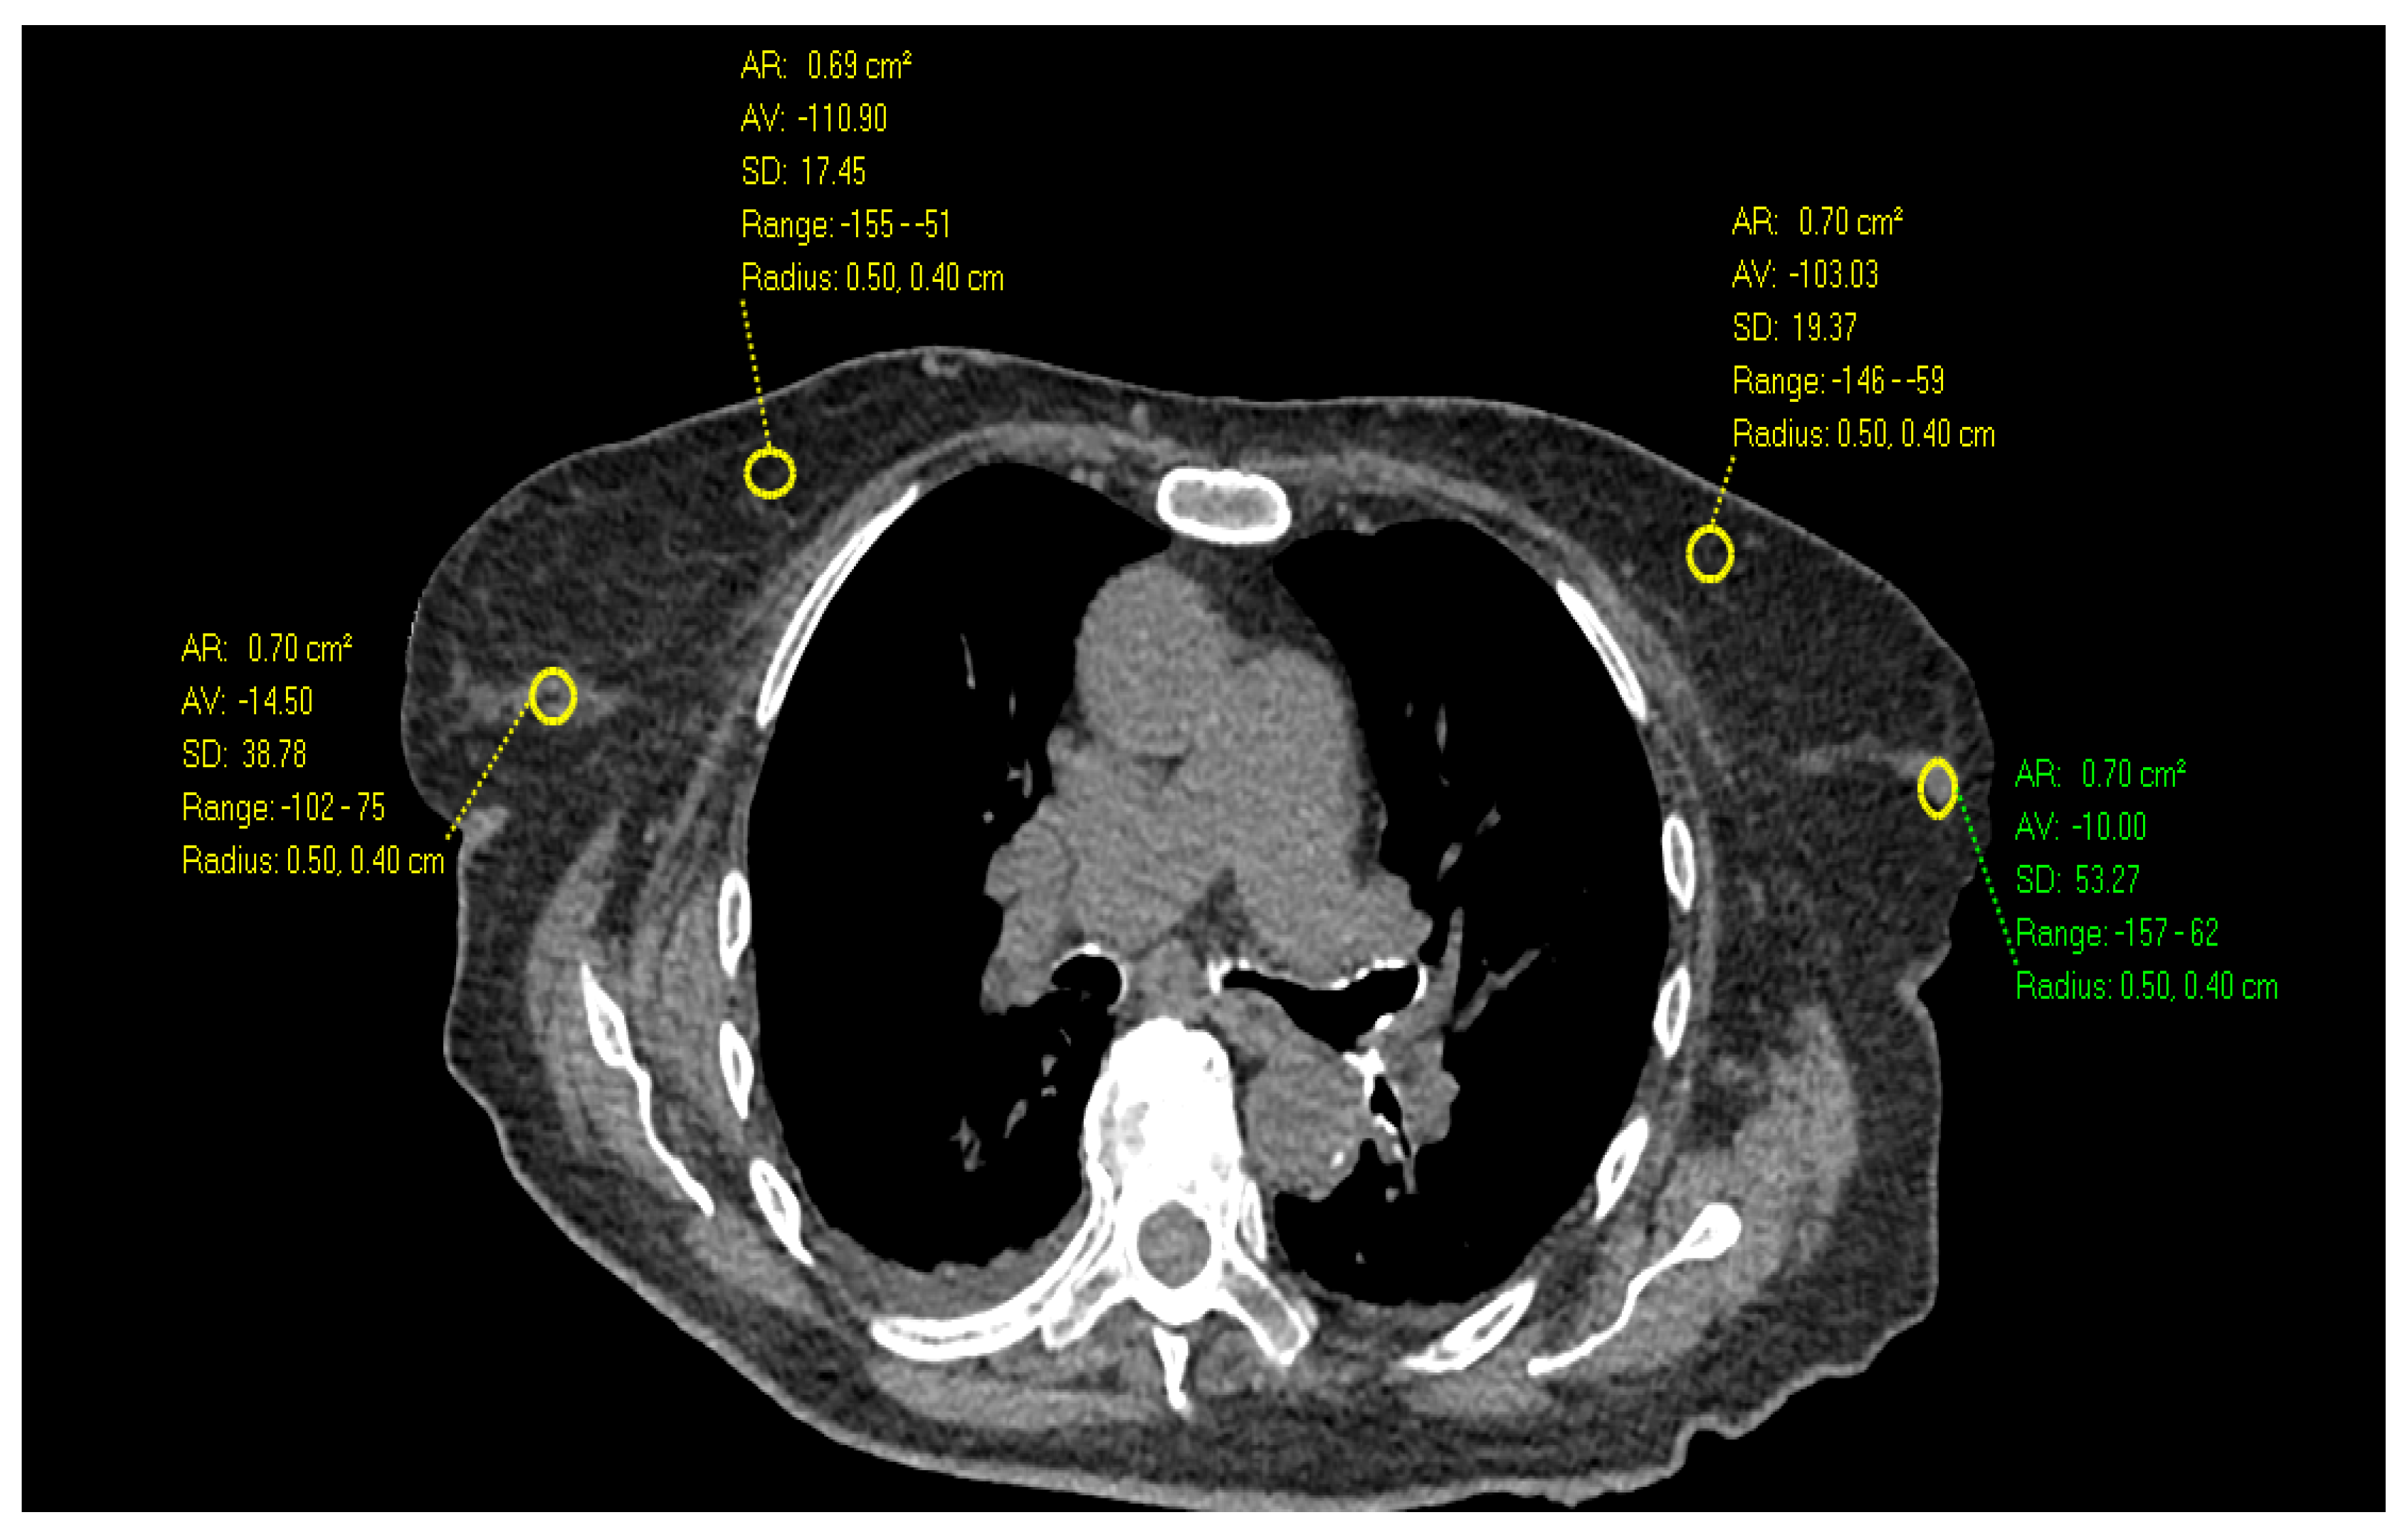

- Desperito, E.; Schwartz, L.; Capaccione, K.M.; Collins, B.T.; Jamabawalikar, S.; Peng, B.; Patrizio, R.; Salvatore, M.M. Chest CT for Breast Cancer Diagnosis. Life 2022, 12, 1699. [Google Scholar] [CrossRef] [PubMed]